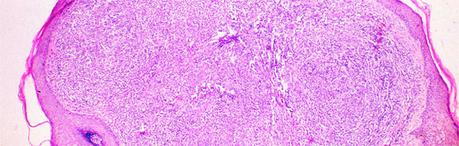

El diagnóstico exacto del granuloma piógeno sólo se puede realizar mediante el estudio histológico de la lesión. Para tal efecto se realiza la excisión quirúrgica de la tumoración y se remite al anatomopatólogo.

En el análisis histológico encontramos una proliferación vascular localizada superficialmente en la dermis. Esta proliferación consiste en una nueva formación de capilares envueltos por una capa simple de células endoteliales.